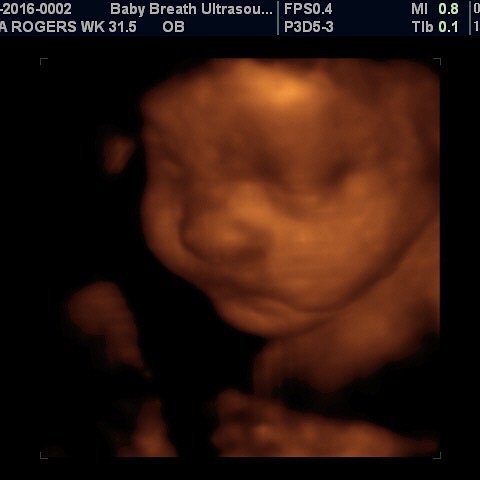

Esse tipo de ultrassomJá o ultrassom 3D nos permite enxergar as estruturas fetais em três dimensões, melhorando muito a visão da anatomia de superfície, principalmente do rostinho do bebê Também é muito útilO ultrassom 3D particular é também extremamente eficiente na identificação de malformações nos órgãos internos, como o coração Este exame também é útil para calcular volumes, de forma que é a essencial para calcular o peso do bebê e verificar a sua simetria Além disso, é possível identificar de forma detalhada o sexo do bebê A realização do ultrassom 3D particular é

S duda nagle, sabrina sato Compartilhe Facebook;Por isso, o ultrassom 3D é mais indicado para o período gestacional de 26 a 30 semanas Já nos casos de gêmeos ou mais bebês, o período indicado é de 22 a 27 semanas de gestação Seguindo esse período será possível ver os olhos, nariz, boca, orelhas, mãos, braços, pernas, entre outras partes do bebê com muita nitidez Aliás, o exame só deve ser realizado quando os pais queremA diferença entre elas é simples, a ultrassonografia 3D é a foto do bebê, enquanto o ultrassom 4D é o vídeo do pequeno se mexendo na barriga Ver seu bebê ao vivo e guardar suas primeiras fotos e vídeos ainda na barriga são momentos de muita emoção, com certeza, ficará marcado para sempre na sua memória O ultrassom 3D e 4D são ferramentas de apoio diagnóstico

Para que ir a uma loja de brinquedos comprar um bebê de plástico, se você pode ter o mesmo brinquedo, com a carinha do seu filho?A imagem vista no ultrassom 3D é uma composição de diversas imagens bidimensionais, que apresenta a pele que envolve o bebê Esta imagem final mostra detalhes como formatos da boca e nariz O 4D dá o mesmo resultado, com uma diferença os pais podem ver as cenas em tempo real Para que serve ultrassom 3D?GRAVIMAGEM LIGUE DAS 08 HS AS 16 HS MARQUE HORA!

O ultrassom 3D e 4D permitem transformar as imagens convencionais (2D) em imagens de cunho tridimensional, permitindo que as futuras mamães consigam ver uma imagem muito mais realista da criança As imagens possuem uma qualidade muito semelhante a uma fotografia e são uma forte aliada para conter a ansiedade de muitos pais que não veem a hora de conhecer o bebê! Desde a chegada do ultrassom 3D, nos anos 1990, os pais puderam diminuir um pouco essa espera De lá para cá, o exame foi aprimorado agora é possível também observar o nariz na ultrassom Meninas, com 24 semanas eu fiz uma ultrassom e o medico ficou encantado com o nariz do meu filho, disse q era afilado, foi us 3D Agora com 34 semanas eu fui fzr uma us normal com outto medico, e ele disse que era de bola Sera se tem como mudar tao rapido?

Acertou dos meus dois bebes Menino e menina!! De acordo com Sebastião Zanforlin Filho, o ultrassom 3D é diferente da ultrassonografia comum, que mostra uma fatia do feto "O exame tridimensional usa o aparelho que capta várias fatias Essas várias fatias, no computador, permitem ver a imagem por fora do bebê Já com o ultrassom 4D, a imagem tridiomensional é feita em sequências muito rápidas Se o bebêPor isso, não deixe de agendar sua Ultrassom 3D!